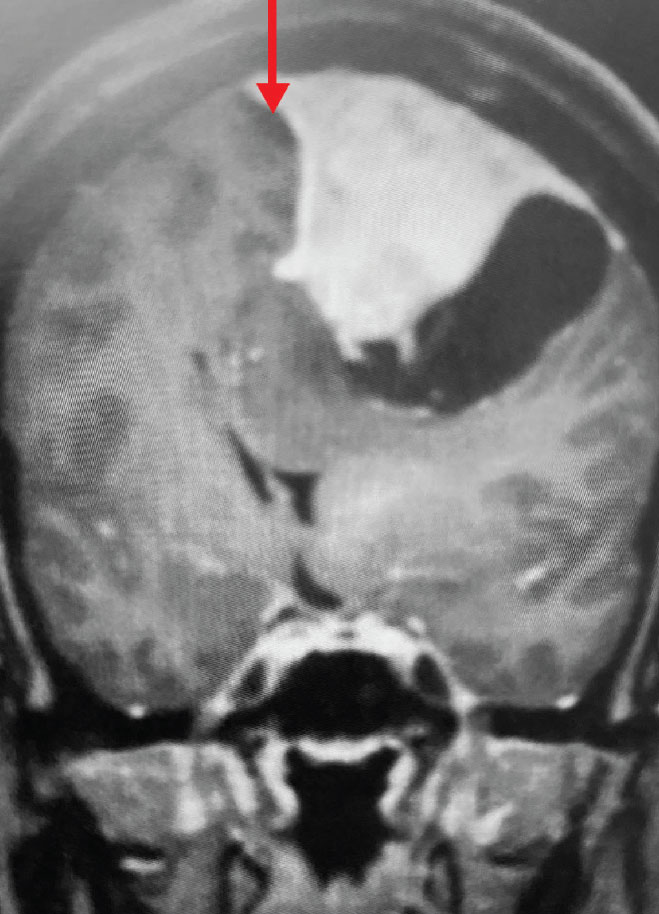

Fig 2. B) Post-operative, post-contrast, coronal MRI.

Treatment: Given the size and location of this tumor, the best treatment was surgical removal. Surgery was performed by Dr. Michael Brisman. A craniotomy exposed the tumor along the convexity as well as the superior sagittal sinus. The tumor was removed, as was the involved convexity dura and the affected segment of the sagittal sinus. Removed dura and skull were replaced with duraplasty (with artificial dura) and a titanium mesh cranioplasty.

Outcome: The patient did very well and made a full recovery.

Summary: Meningiomas, even when very large, are usually benign tumors. In cases of large meningiomas, surgical removal can lead to dramatic improvement in symptoms and can be curative.